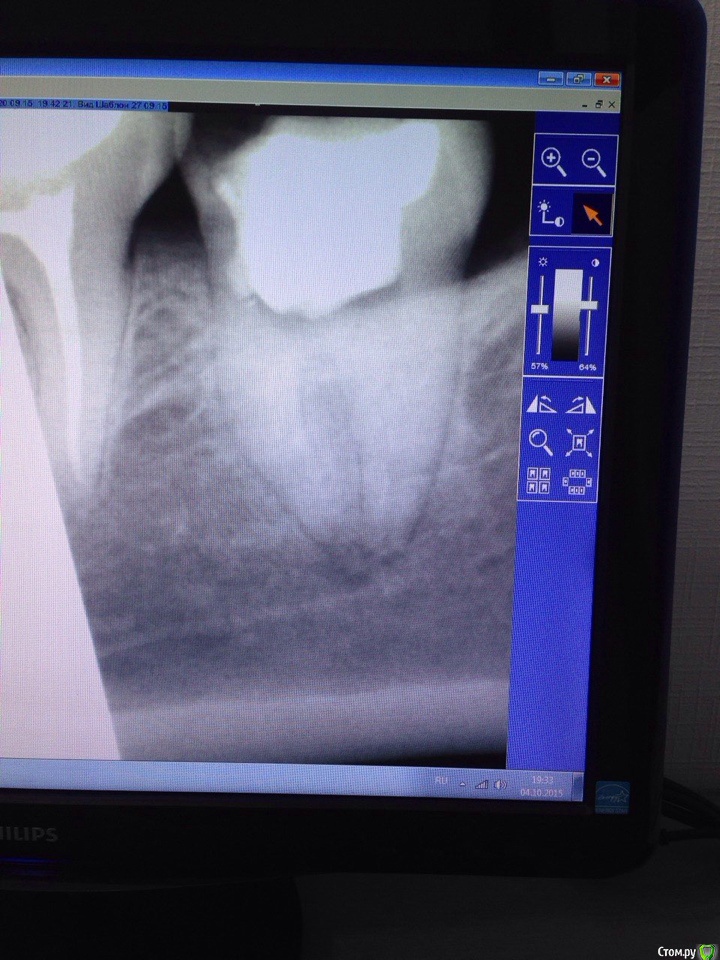

DA89 Опубликовано 12 ноября, 2015 Автор Поделиться Опубликовано 12 ноября, 2015 Нужен снимок после удаления и фото хорошего качества. прицельный37.bmp Ссылка на комментарий

red_butler Опубликовано 12 ноября, 2015 Поделиться Опубликовано 12 ноября, 2015 На снимках все не так уж плохо, но для выбора дальнейшей тактики нужен очный осмотр. Альвеолиты иногда, к счастью редко, носят затяжной характер. Ссылка на комментарий